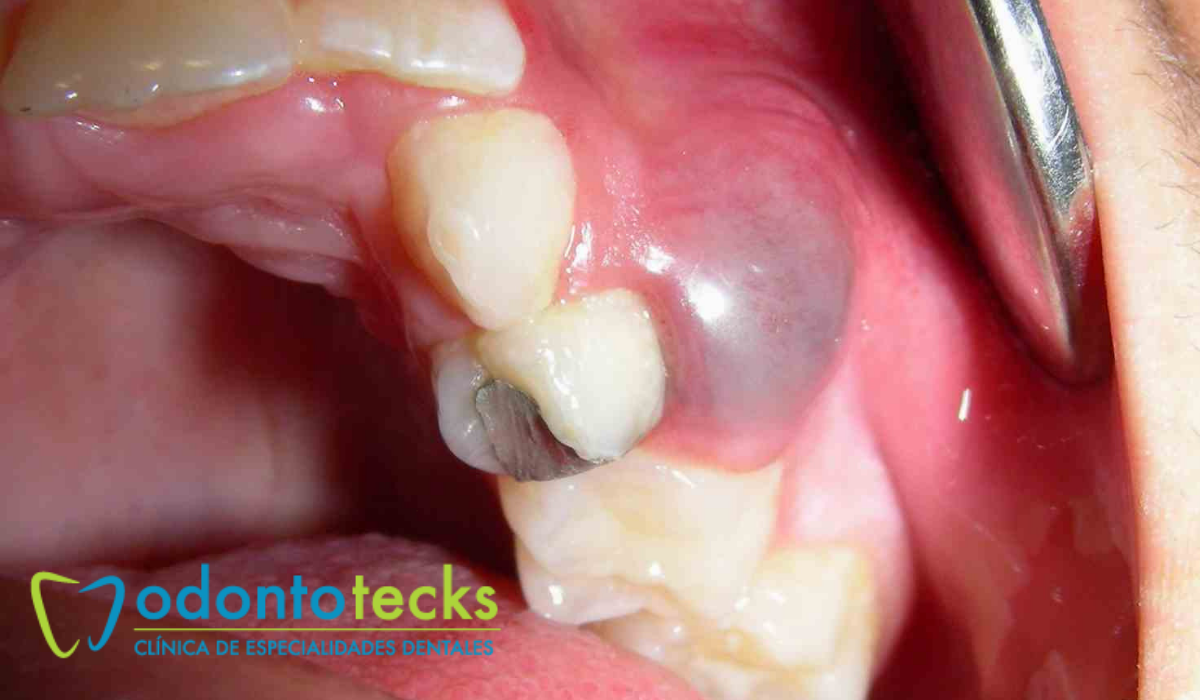

Al tratarse de una condición crónica, en la mayoría de los casos los quistes dentales no producen síntomas, pero pueden llegar a causar molestias y dolor si se llegan a infectar. Los quistes son cavidades que se pueden expandir a dimensiones considerables y lo hacen a expensas del hueso, consumiéndolo a medida de que crecen. Los de mayor tamaño pueden llegar a producir pérdidas importantes de hueso e incluso crear perforaciones.

El tratamiento de un quiste dentario siempre consiste en su eliminación, ya que estas estructuras tienen la capacidad de producir pérdidas de hueso que comprometen la estabilidad de los dientes vecinos, además de que tienen el potencial de tornarse en lesiones malignas.

Cuando el diente afectado está muy destruido y no tiene posibilidades de restaurarse, se hace su extracción luego de lo cual se elimina el quiste y se limpia el hueso. Los quistes periodontales se pueden eliminar sin hacer ningún tratamiento sobre el diente, ya que son condiciones que no los compromete.